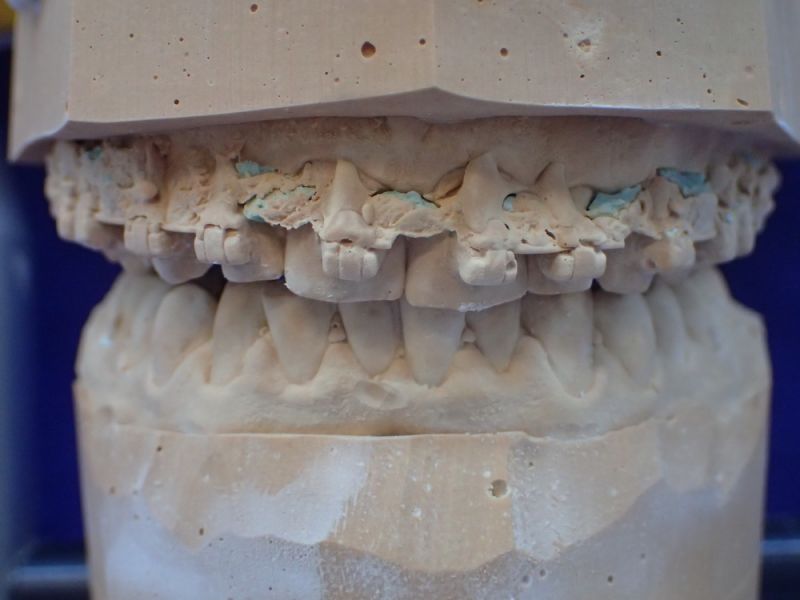

Es erfolgt dieErstuntersuchung und die Herstellung und Eingliederung eines adjustierten Aufbissbehelfs zum Nachweis einer CMD.